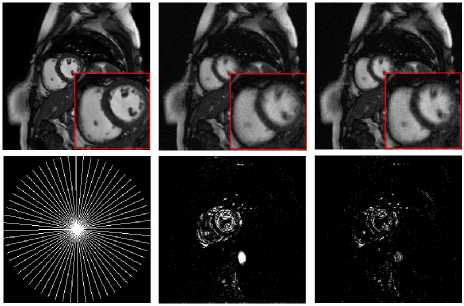

In Fig.1, we compare the recovery results of the TMNN with MNN on a cine cardiac MR image from 30 radial lines (undersampling ratio 0.1) in the noiseless case. We observe that the proposed TMNN model outperforms the MNN method in providing more accurate reconstruction. Fig.2 shows the reconstruction of the cine cardiac MR image from the noisy undersampled measurements using 30 radial lines. In Fig.3, we plot the noisy reconstruction results of the perfusion MR image from the variable density random sampling trajectory with the undersampling ratio of 0.3. It is observed that the TMNN method generates less error compared with the MNN approach. The SNRs of the reconstructed dynamic image using TNN, MNN, and the proposed TMNN at different undersampling conditions are shown in Table.1. We observe that except for one case, the proposed TMNN consistently provides the best reconstruction results and improves the SNR by up to 2dB over the MNN method. In addition, it is shown that the improvement of the proposed TMNN over MNN is more significant in the noisy setting.

Fully sampled MNN recovery TMNN recovery